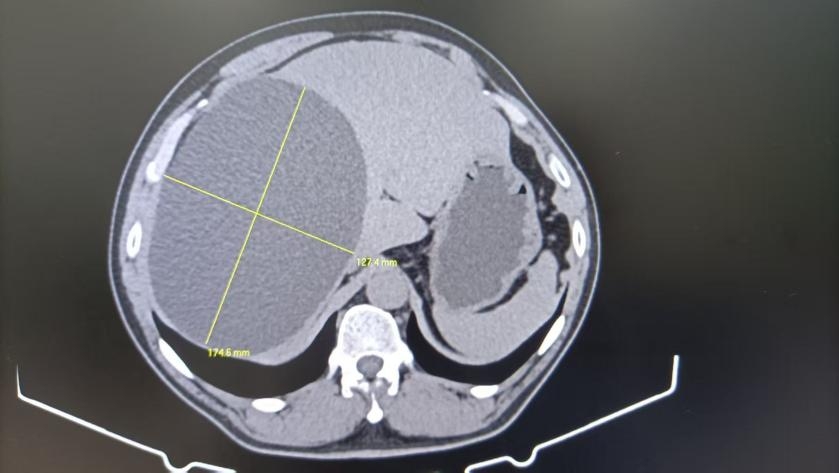

肝囊腫是指在肝臟內形成的充滿液體的囊狀結構。是較常見的肝良性疾病,大多數情況下不會引起明顯的癥狀。肝囊腫可以是單發的,也可以是多發的,大小從幾毫米到十幾厘米不等。

2. CT掃描:提供更詳細的圖像,有助于區分囊腫的性質。